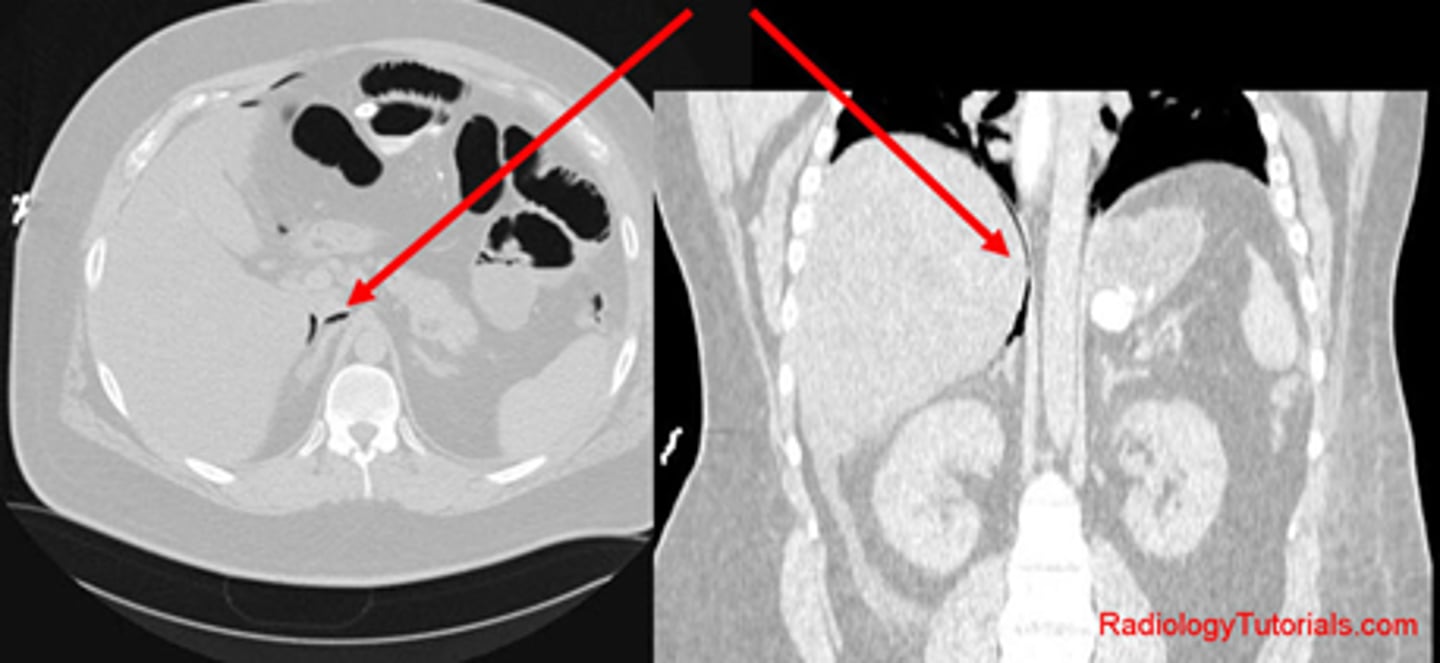

A:

WHITE ARROWS: soft tissue mass on LUQ

BLACK ARROW: displacement of bowels to the right

B: CT of the same patient

WHITE ARROW: large renal cyst arising from left kidney, displacing it and surrounding bowel.

BLACK ARROW: left kidney.

S: spleen, compressed by cyst.